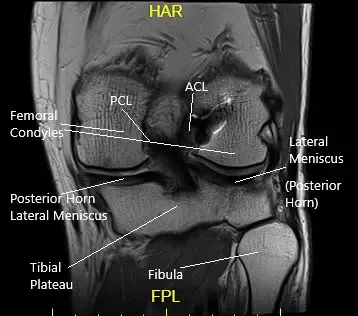

Le realizaron una resonancia magnética que mostró desgarros del menisco medial en la unión meniscocapsular y la unión posterior cuerno-cuerpo. Hubo pérdida de cartílago tricompartimental.

Vista de la resonancia magnética coronal de la rodilla izquierda.